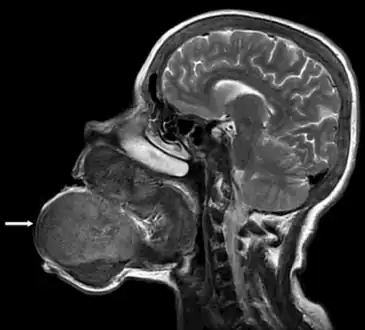

Image showed that the brown tumor originated from the mandibular and maxillar bones

Radiographically, brown tumor may show no detectable changes or a generalized osteoporosis. Partial loss of lamina dura around the teeth may occur but is not a constant feature. Focal Lesions (Brown Tumor) present as sharply defined, round or oval radiolucent areas which may appear multilocular. Such lesions occur more frequently in mandible than maxilla [7]